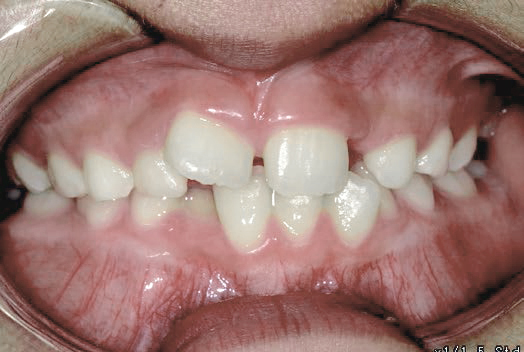

歯がガタガタに並んでいて、前歯の真ん中の位置が少し左にずれていました。

奥歯が生えるためのスペースが足りず、永久歯が生えて来られない状況が確認できました。

また、飲み込むとき下くちびるに力が入ってしまうクセが見られ、お顔全体の成長が遅れている様子が確認できました。

治療を終えて

歯がきれいに生えるためのスペースをしっかり確保することができ、歯並びを乱していたお口のクセも改善されたため、奥歯が生えるスペースを確保することができました。

しっかり噛めるかみ合わせを作ることが、将来の健康につながるので「よく噛む」練習も続けてもらっています。

主訴・治療内容 歯がガタガタになってきたことに悩み、無料相談に来院されました。

治療期間 3年

費用 462,000円(税込)